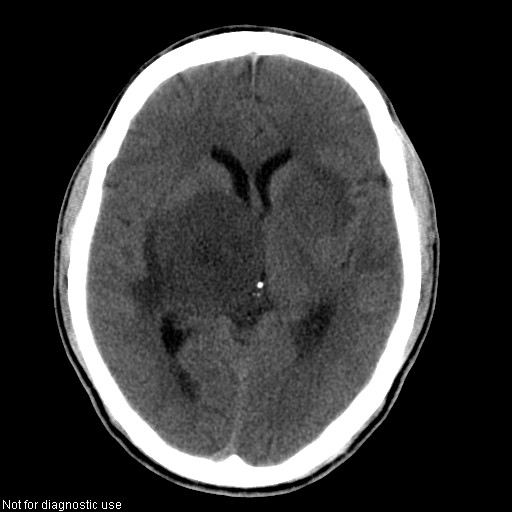

以下是引用hhcckk在2008-1-26 16:03:00的发言:[br]考虑病毒感染可能性大[br]1、病人发病时间短,1周,转移病灶时间长[br]2、楼主虽然没有告诉我们年龄,但从颅内情况来看,病人年纪不会很大,脑池,脑沟不是很明显,当然,可能有脑肿胀的原因,转移灶病人年纪一般较大[br]3、从病灶特点来看,转移多发生在灰白质交界区,多有指状水肿,占位效应明显,此病人呈对称性发布,发生在脑实质深部,与转移有所区别[br]4、病人经抗炎,止咳效果不好,可能是病毒感染,抗生素治疗效果不好[br]5、建议楼主1、增强 2、有呼吸系统的症状何不拍个胸片